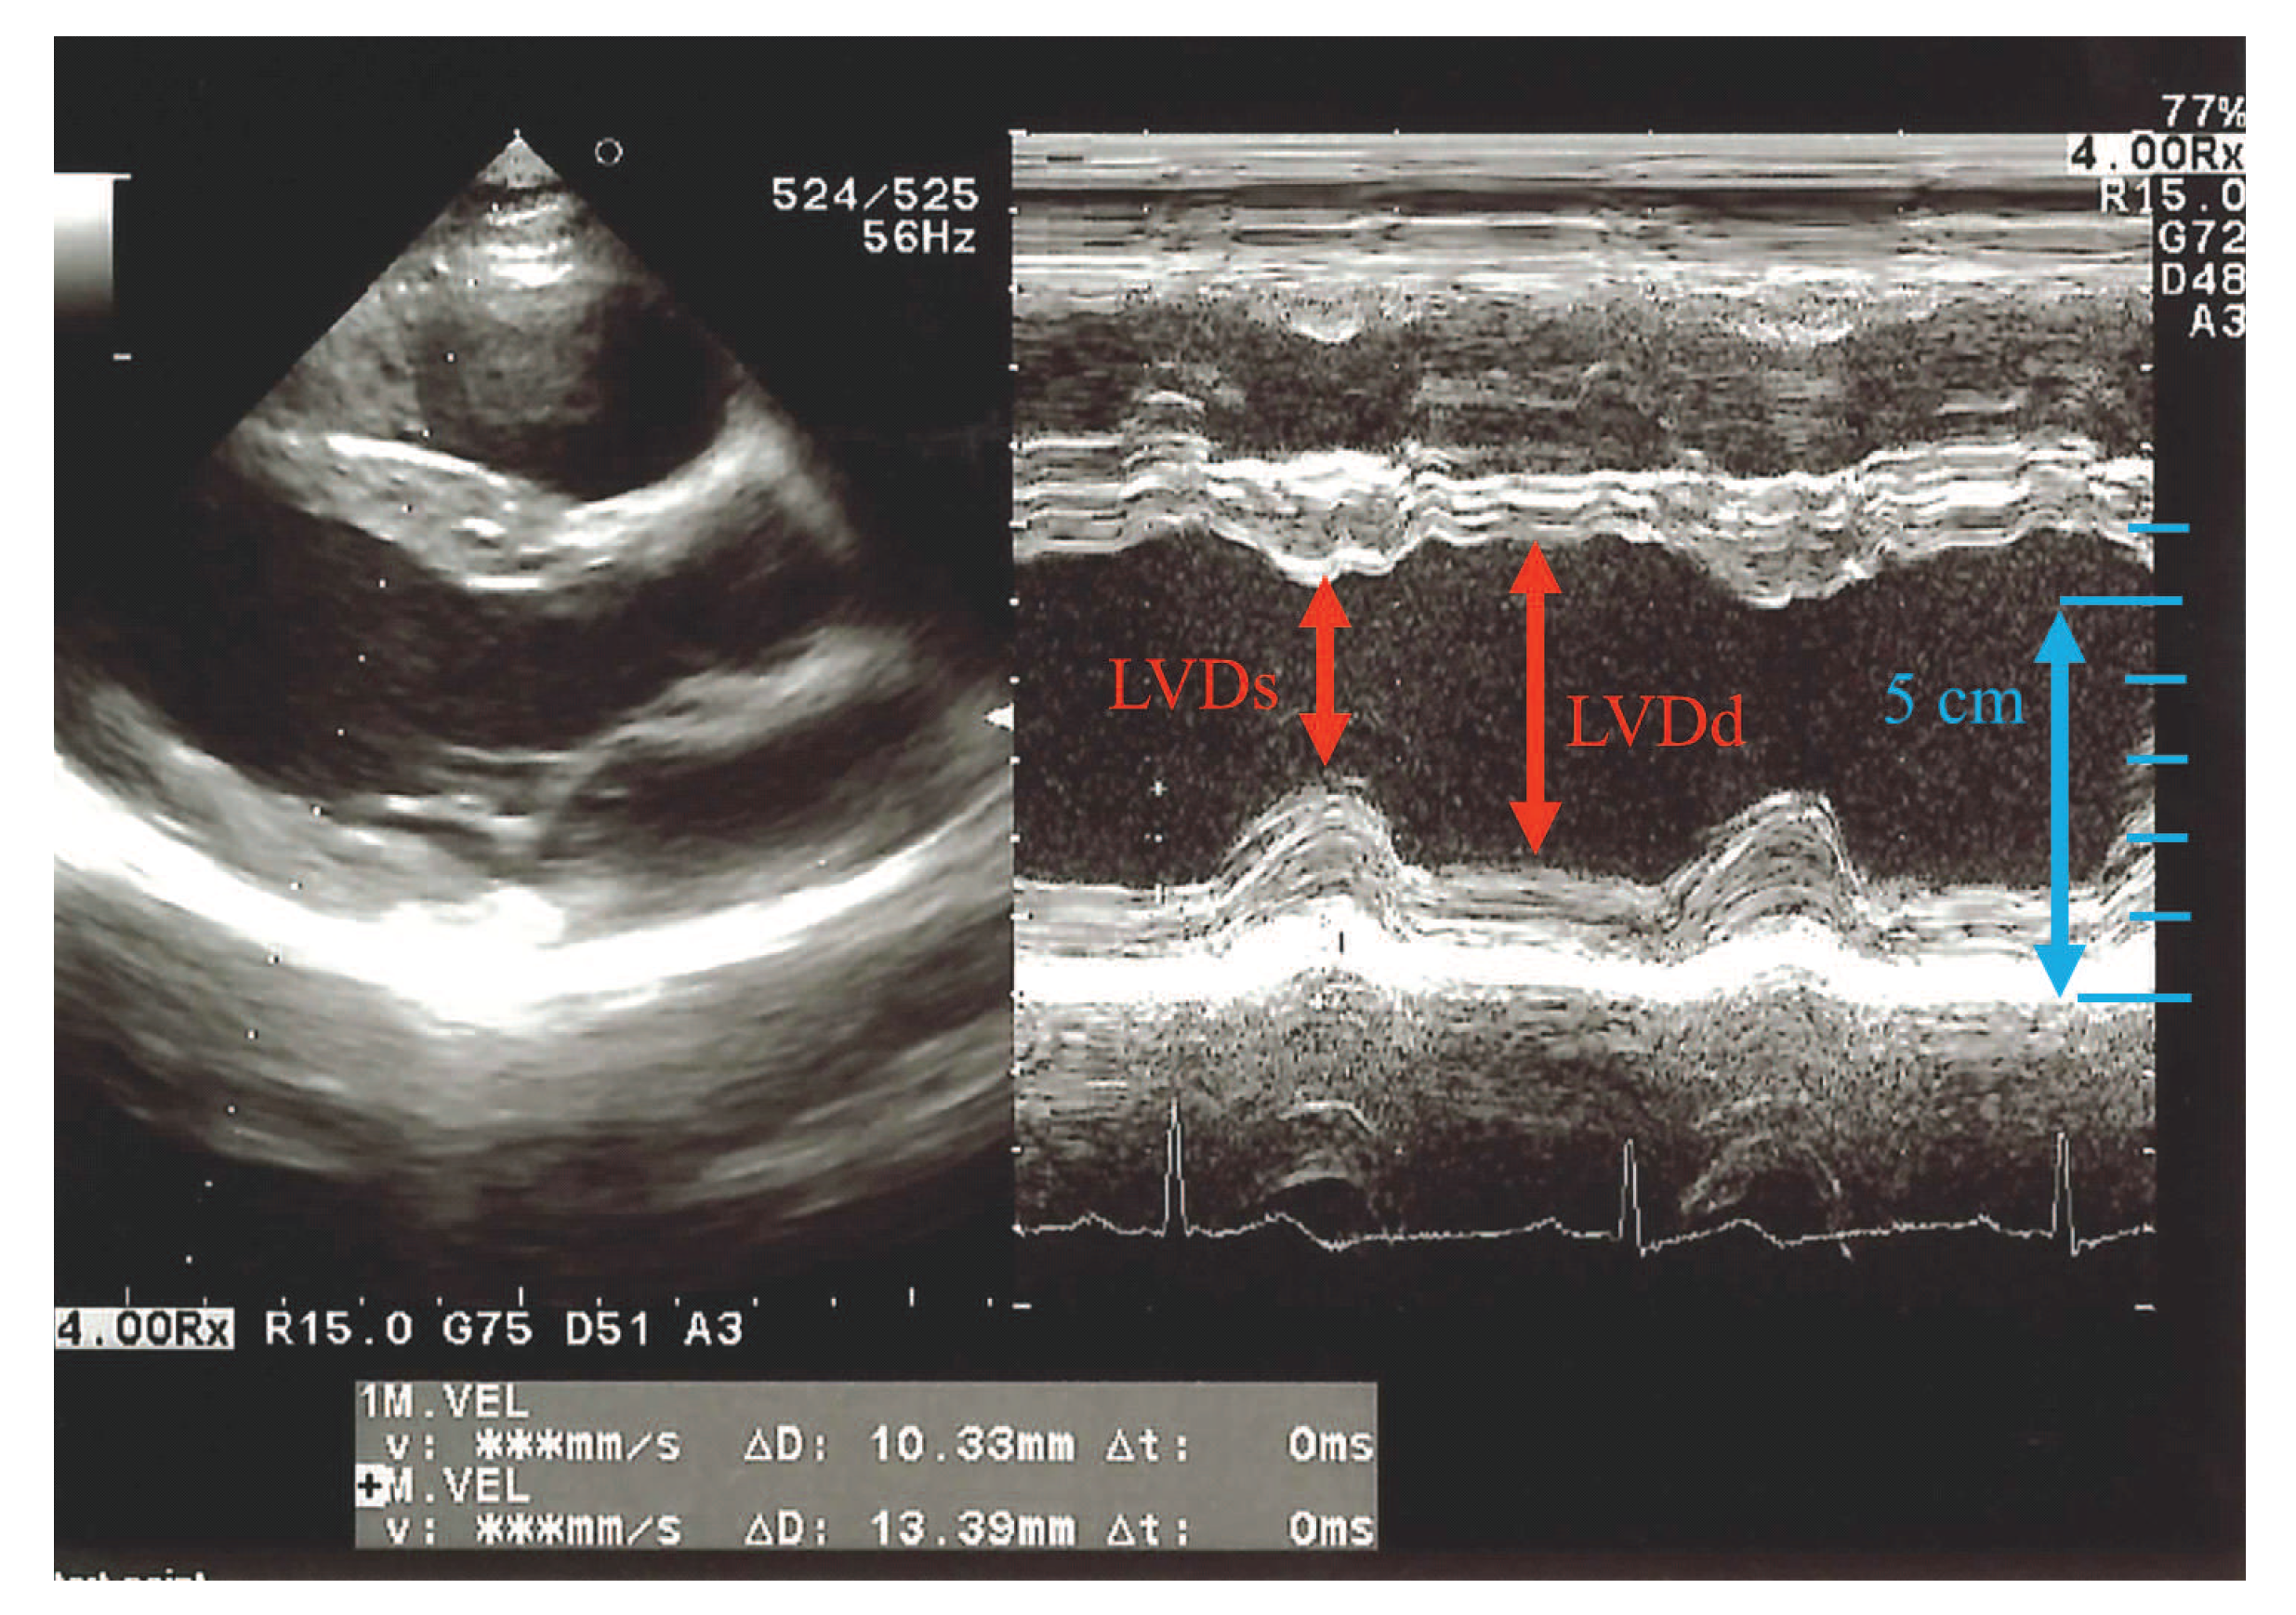

When a microwave wave is applied to the human chest, the microwave wave reaches the back by passing through the human body and diffracting around the human body. Since the internal structure of the human body changes during diastole and systole [21], it is believed that the microwave waves that reach the back change with the heartbeat. Figure 1 shows the diastole and systole of the left ventricle of the heart on the time axis by ultrasonic measurement. The left ventricle has a part where the anterior wall and posterior wall are contracted. This part is where the heart is beating and there is a displacement of 2 cm in total in the front and back. Since the human body structure around the heart changes due to this diastole and systole, it is possible to capture changes in the internal structure of human body by irradiating the human body with microwaves and acquiring microwaves that pass through the heart. To confirm this consideration, an electromagnetic field simulation with an anatomically-based human body model was performed. The numerical human body model consists of more than 50 tissue types with a resolution of 2 mm [22]. Here this model was used for diastole. On the other hand, the diameter of the heart of the human body model was reduced by 2 cm, and the part caused by the reduction was filled with air instead. This model was used for systole. The electromagnetic field simulation was performed using the finite difference time domain (FDTD) method [23] for the two models. The dielectric properties were cited from Gabriel [24].

Figure 1.

Ultrasonic image of left ventricle of the heart.